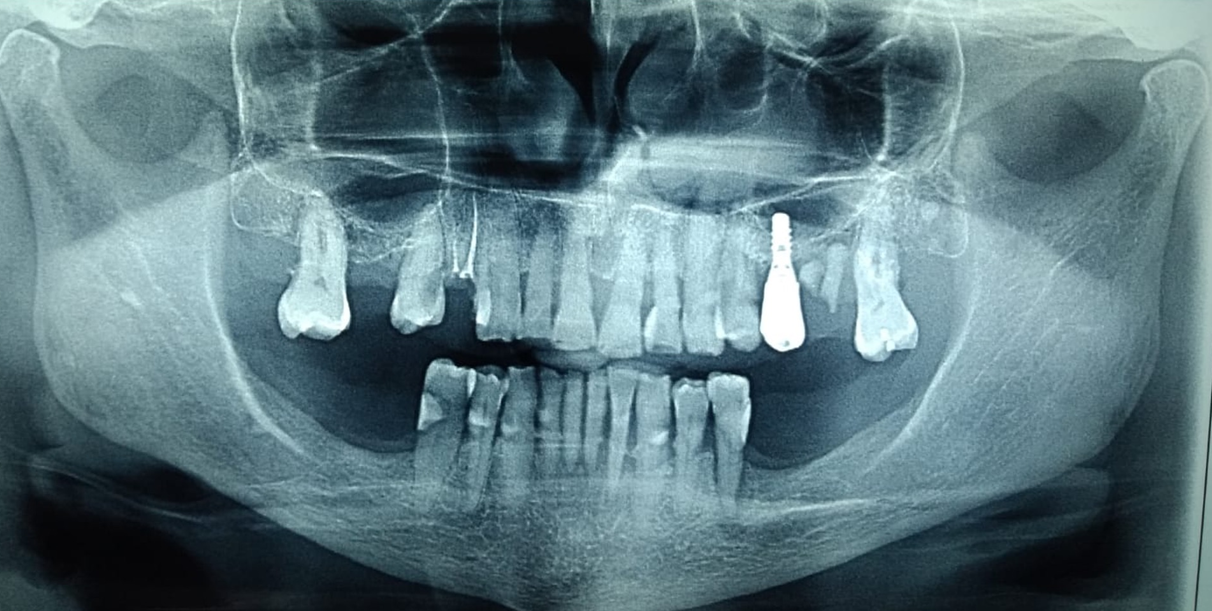

Diagnóstico: Riesgo y actividad de caries. Diagnóstico periodontal: Periodontitis estadio II grado A Generalizada. Diagnóstico oclusal: brechas desdentadas, plano quebrado por extrusión de molares superiores (17 y 27).

Radiografía seriada

Radiografía panorámica